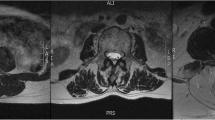

In this retrospective study, we randomly selected 60 MRIs (39 women and 21 men) of the lumbar region from a sample of a large cohort study, which was approved by the local ethics committee (EA1/058/21). MRI scans were conducted using a Siemens Avanto 1.5 T MRI system (Siemens AG, Erlangen, Germany) with T2-weighted turbo spin echo sequences for both axial and sagittal images. The axial T2 parameters used were a repetition time of 4.000, an echo time of 113, and a slice thickness of 3 mm. As the vast majority of degenerative changes can be detected in the lower spine, the levels L4–L5 and L5-S1 were evaluated.

All measurements were performed by two orthopedic residents, who were trained in the MRI muscle assessment. The MRI images were measured through the two different image processing programs (ImageJ and Amira). The two observers measured the MRIs in a random order for both investigators. The CSA of the multifidus muscle (MF) and erector spinae muscle (ES) was measured at mid-disk level L4/5 and L5/S1 (Fig. 1), the CSA was single measured before applying any thresholds. FCSA and FCSA/CSA were determined using two different segmentation thresholds for differentiating muscle fibers and fatty muscle infiltration.